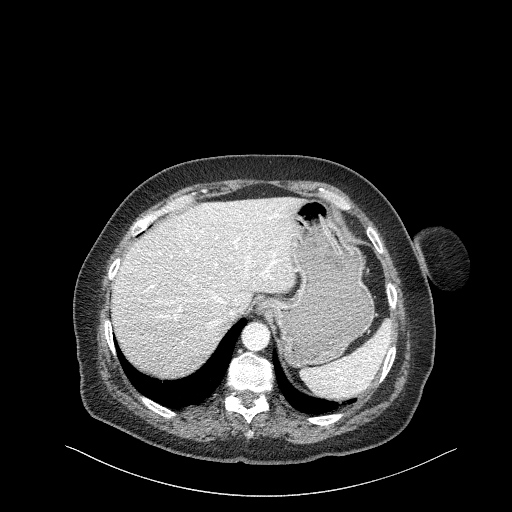

Original VENOUS CT scan

Full window (WL 1023.5, WW 4095 β Low β1024, High +3071)

Actual HU range: [-160.0, 240.0]

Lung window (WL -600, WW 1500 β Low β1350, High +150)

Actual HU range: [-160.0, 150.0]

Mediastinum window (WL 40, WW 400 β Low β160, High +240)

Generated VENOUS CT scan (AβB translation)

Actual HU range: [-855.0, 775.1]

Actual HU range: [-855.0, 150.0]